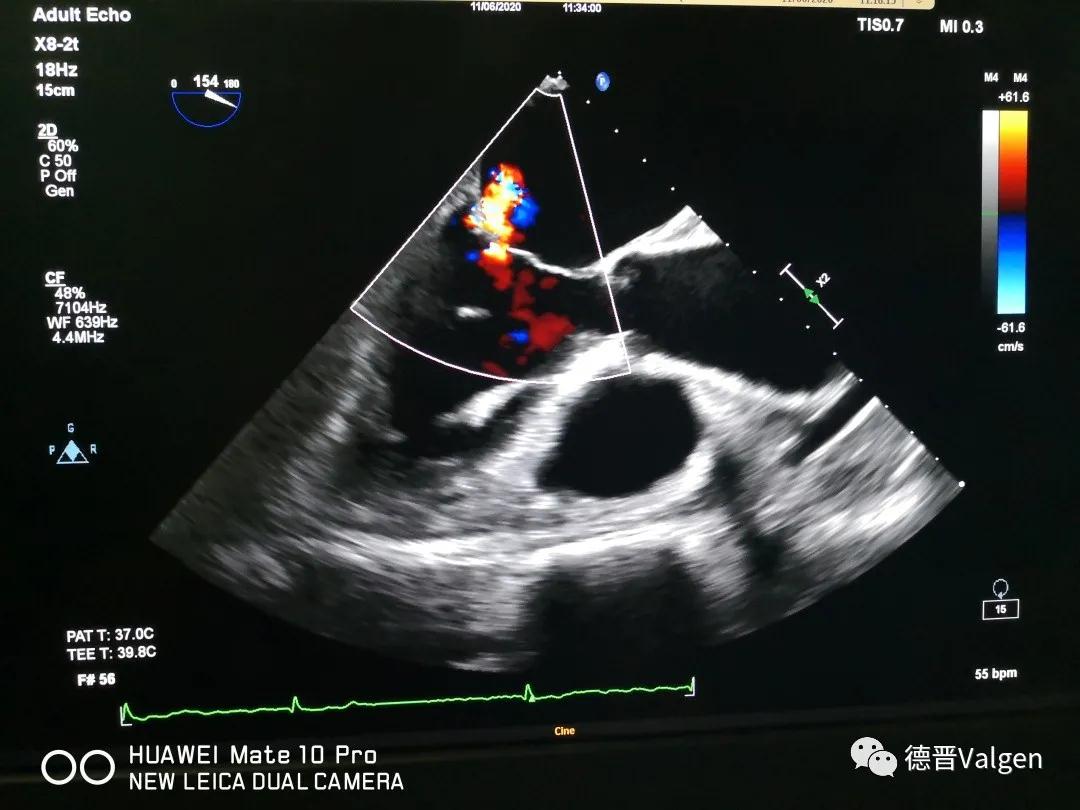

突破!华西医院陈茂教授团队成功开展Dragonfly™手术

德晋医疗专注于结构性心脏病领域尤其是二尖瓣和三尖瓣的相关治疗技术的研发,提供二尖瓣病变系统性解决方案(Tool Box Concept)。德晋医疗曾研发了中国第一款微创介入治疗二尖瓣反流的产品(MitralStitch®),并于2018年1月份成功应用于人体临床。DragonFly™为中国第一款经股静脉二尖瓣缘对缘修复器械,优化的输送系统,使产品可同时应用于三尖瓣介入治疗。德晋医疗成为了国际上唯一具备两种成熟的二尖瓣介入修复器械的公司。德晋医疗的其他二尖瓣和三尖瓣相关器械也在研发当中,公司致力于创新型二尖瓣微创介入治疗全套技术研发,全力推动结构性心脏病治疗领域的发展,让中国智造,惠及世界。